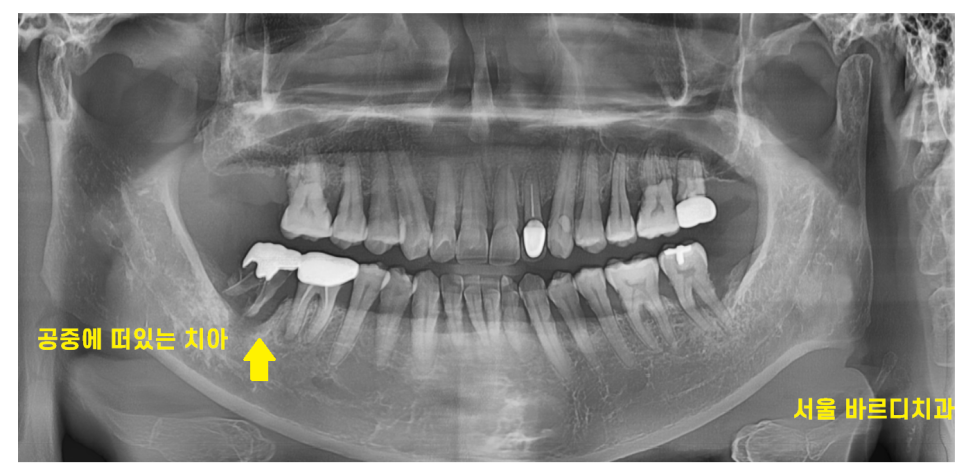

x-ray로 확인해본 결과

공중에 떠있다고 봐야할 정도입니다.

이러니 이 흔들림이 발생했죠..ㅠㅠ

문제가 되는 맨 끝 치아

금니로 씌운 것을 봐주세요~

치아 뿌리가 다 보이시죠~?

충치도 보이고..

잇몸뼈가 많이 녹은게 보입니다.